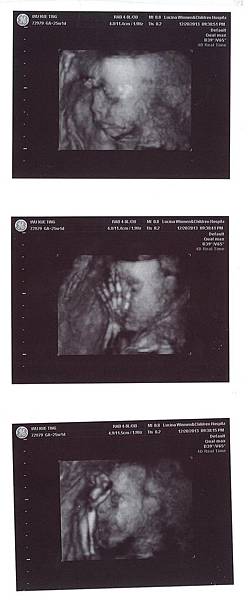

小樂樂3D照-25+1D

25W+1D 做了妊娠糖尿的檢查也第一次看到樂樂本尊的模樣

小妮子...有哥哥的影子,只是目前還沒長肉~~

小寶貝呀~~你就努力吸收吧!媽咪會好好節制的...